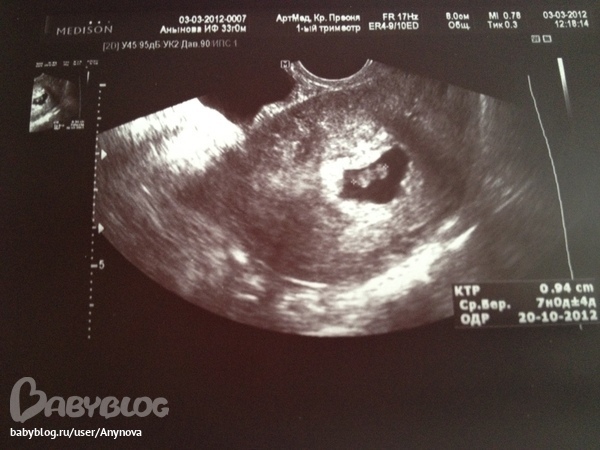

Узи 6 недель нет сердцебиения

Узи 6 недель нет сердцебиения 119 фотографий